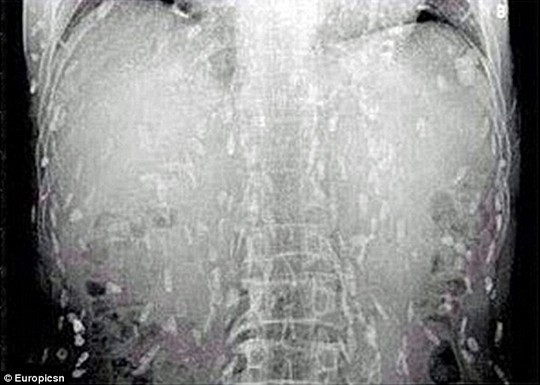

Sán xuất hiện khắp cơ thể người đàn ông

Trước đó, người này đã đến bác sĩ khám và than phiền về việc đau bụng, ngứa da. Kết quả quét toàn bộ cơ thể cho thấy sán dây ký sinh trên khắp cơ thể của bệnh nhân. Người này cho biết trong thời gian dài, anh là tín đồ của món sashimi (cá sống). Do đó, các bác sĩ tin rằng nguyên nhân người đàn ông nhiễm sán là do ăn quá nhiều cá và thịt chưa nấu chín kiểu Nhật.

Bác sĩ Yin công tác tại Bệnh viện Nhân dân số 8 Quảng Châu cho biết người ăn thực phẩm chưa nấu chín có nhiễm trứng sán dây sẽ mắc bệnh giun sán. Khi trưởng thành, sán nhiễm vào máu người. Tình trạng này có thể đe dọa tính mạng khi sán nhiễm lên não người.